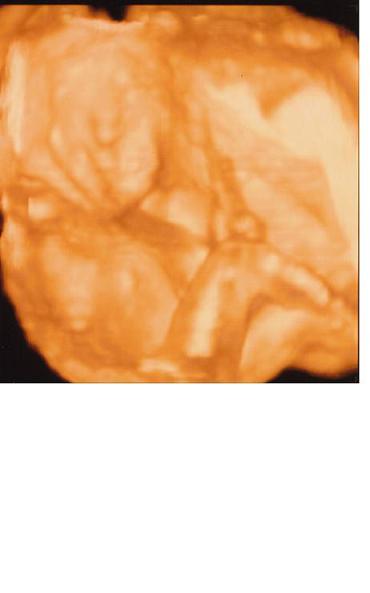

Ma voltunk a genetikai uh-n es 3d-n. Minden rendben talaltatott, mindene megvan, noha nehez volt vegig kovetni, mert nagyon ficankolt. Az uh-s neni azt mondta, vegyek sok sportcipot! :lol:

Vegre rajottem, hogy lehet kepet felrakni, ugyhogy ime a fotok:

Azt hiszem, nem kell magyarazni, ezen a kepen mi lathato:

Kép